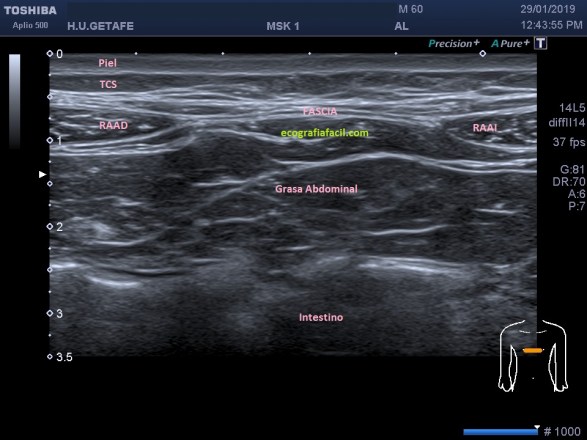

Si tu lo quieres estudiar en un corte transverso o eje corto del tendón verás como muestra de normalidad la imagen número 1. Semiológicamente es muy agradecido. Ves el tendón ovalado, hiperecogénico reposado en la corredera bicipital. El ligamento transverso humeral, hiperecogénico y lineal, anterior a la estructura tendinosa que descansa en la corredera.